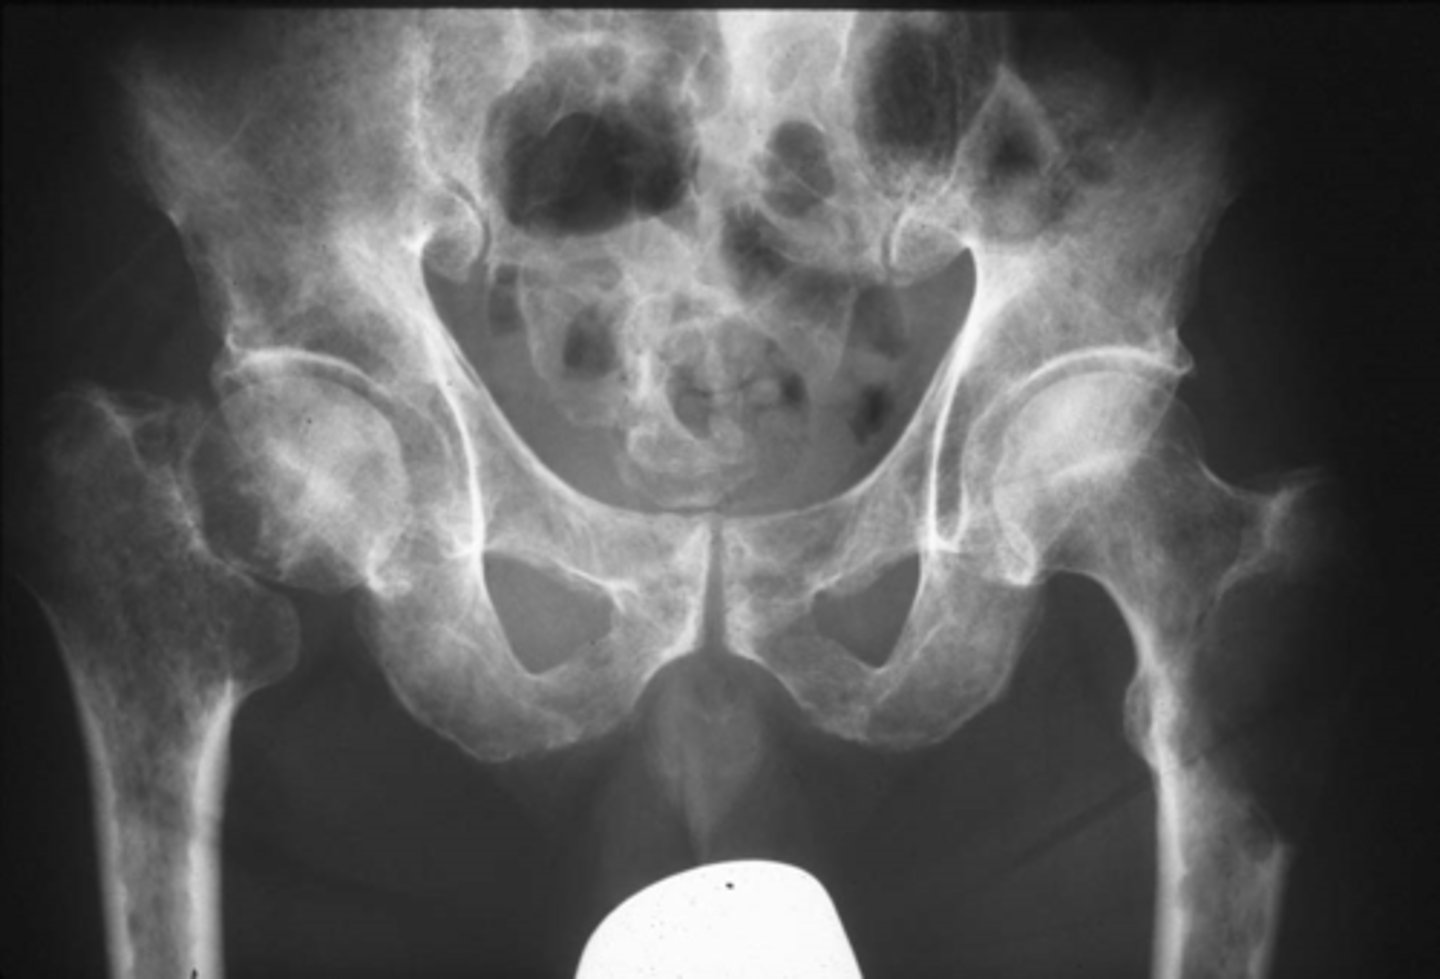

Vignette # 5

Sex: Male

Age: 50

Chief Complaint: Patient presents with hip pain that’s a 6 out of 10 on the pain scale. Objective Findings: Hibbs+, Anvil+

Diagnostic imaging: X-ray

1. List the radiographic signs that you are expecting to see. (Choose 3)

a. Ground glass

b. Osteolytic lesion

c. Joint destruction

d. Osteopenia

e. Metaphyseal Lesion

f. Expansile lesion

g. Cortical thickening

h. Sclerosis

2. What is the most likely diagnosis? (Choose 3)

a. GCT

b. Blastic lesion

c. Primary neoplasm

d. Paget’s disease

e. Fibrous dysplasia

f. Hematopoetic disease

g. Blastic metastasis

h. Multiple myeloma